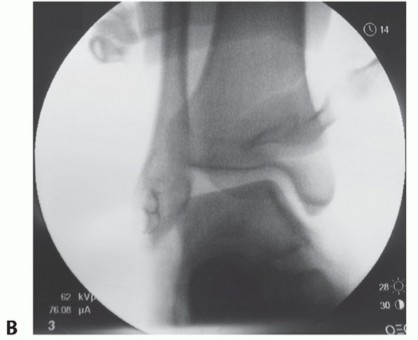

FIG 1 • A. Plain radiograph of an unstressed, non-weight-bearing ankle after injury and before anatomic repair. B. Preoperative stress radiograph of the same ankle demonstrating talar tilt.

The joint (and the contralateral joint) is examined under anesthesia to determine the true nature of instability and also to gauge the effect of the repair (FIG 1*).